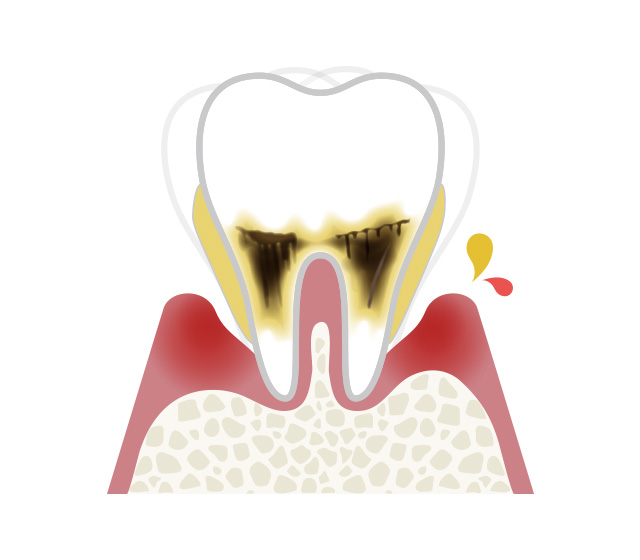

歯ぐきから血が出ていないから大丈夫と思われているかもしれませんが、歯周病は血が出ていなくても進行しています。歯周病はサイレントキラーと呼ばれるほど自覚症状がなく進行してく病気です。

その背景にも関連し、知らず知らずのうちに歯周病が進行し、日本の成人では約80%が歯周病にかかっていると言われています。

歯周病のこと~日本人の80%は歯周病です~